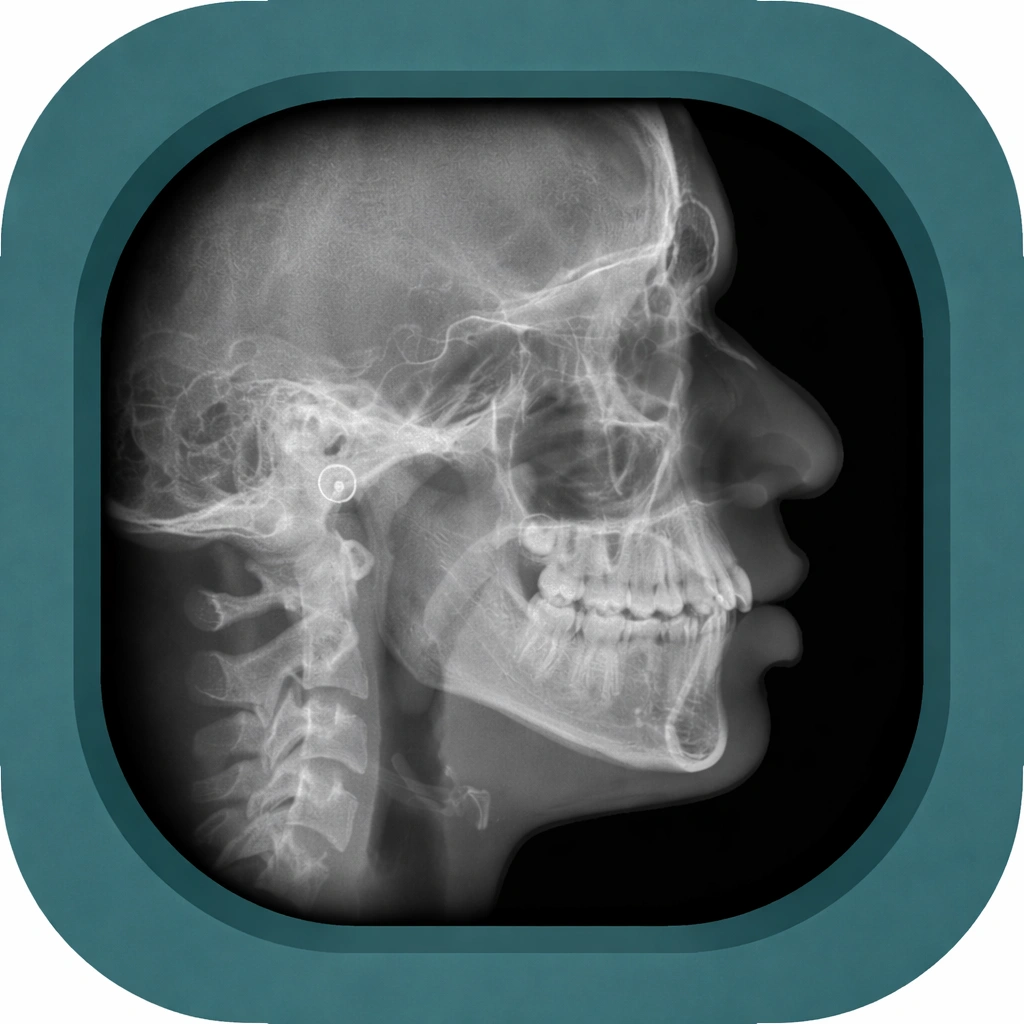

Explore high-quality X-ray anatomy from head to toe. Our database features carefully labelled images to visualize fine structuresโ€”perfect for radiologists, students, and surgeons.